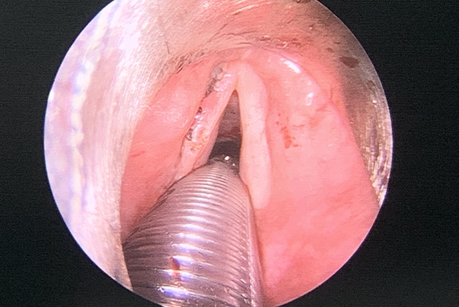

术区无残留病变及活动性出血、异物